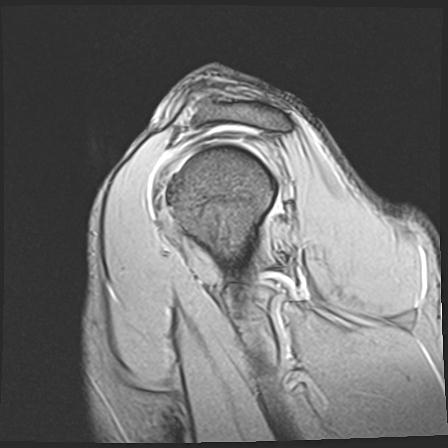

60058 3/9 11/4 右肩 2R+MRI 73歳男性 肩腱板損傷